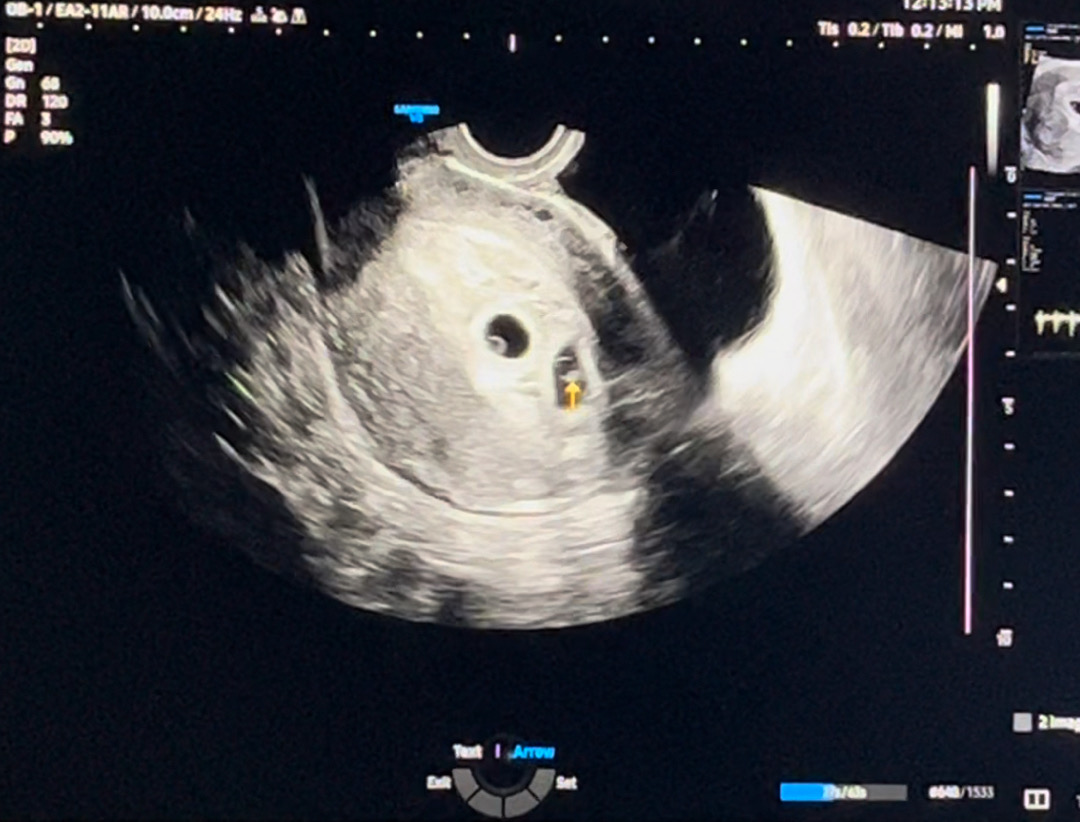

6주3일 심소

12/15 4일배양 2개이식하고 오늘로 6주 3일차에오 1/6일날 둥이인거 확인했지만 센터에 자리잡은 후둥이가 작다해서 걱정했거든요 어제오늘 생리통처럼 배아프고 허리 골반 통증 있어서 서브병원 갔다가 심소, 깜빡임 보고왔어요 후둥이도 정상 속도로 따라왔고 심박수도 둘다 정상이래요~~~ 기쁜 맘에 베동와서 글남겼어요

선둥이 119 / 후둥이 114 선둥이는 6주 4,5일정도 후둥이는 6주 2,3일정도로 둘이 차이가 조금 있기는 해도 정상속도라고 하셨어요 ㅎㅎ

6주는 103-126 7주는 126-149 가 정상범위래요